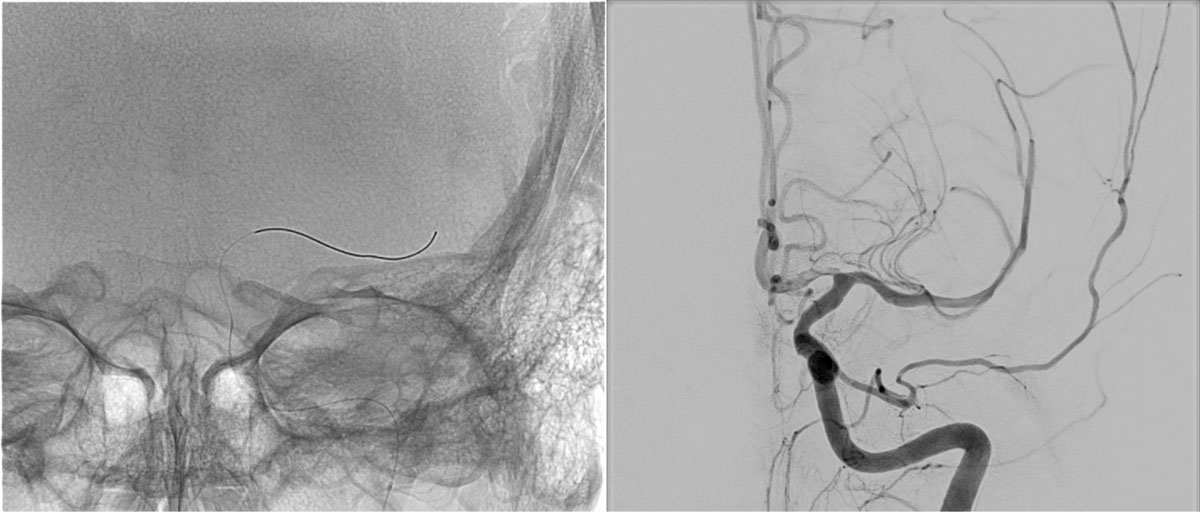

DSA

L - VERT

L - ICA

• BOBBY™ Balloon Guide Catheter

• Select-Sim

EVT Strategy

• Inflate the balloon, in order to dilate the true lumen

• MCA access with the softest system possible

• Open a stentriever for 20 mins with antiplatelet infusion

• Resheath the stentriever, check patency, if not stent-deployment

Headway™ DUO 156cm / Traxcess™ 14

CatchViewMini20

pEGASUS 4x20mm